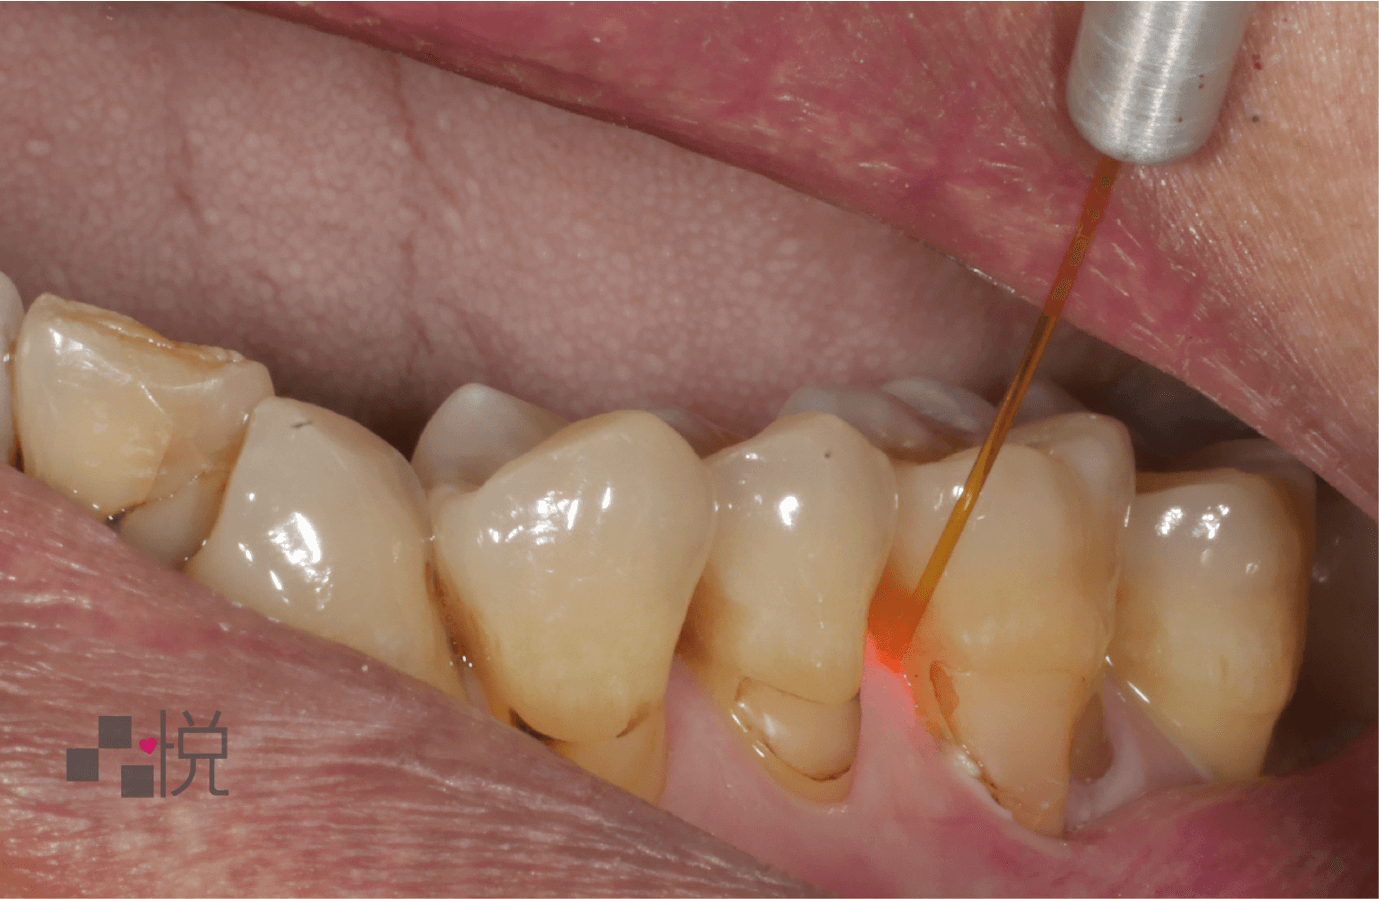

另一種適合牙結石較深處時使用的方法:微創雷射牙周病治療

雷射光深沉清潔牙周病的牙結石

微創雷射深層清潔牙周

(案例提供:品悅牙醫 張真豪醫師)

隨著牙科用雷射的發展,牙周病治療上病患也有了新的治療工具,不同於傳統器械,因雷射儀器較細小,讓醫師在治療中可以不用刀片或翻瓣等動作,達到更深層的牙周清潔,讓治療變得更保守且微創,對患者而言術後的不舒服度低